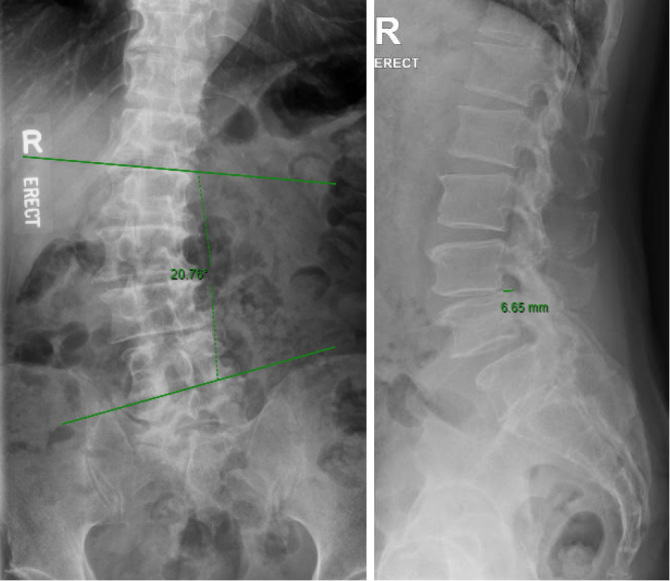

腰椎显微减压术(LSMD)是一种常见的减压神经元件的外科手术。尽管最佳减压程度仍然是一个重要的考虑因素,但有限的循证指南定义了内固定融合以保持生物力学稳定性的阈值。现有研究表明,单侧LSMD一般不会导致医源性不稳定。然而,与双侧节段性减压(BLSMD)相关的潜在不稳定性尚不明确,特别是在已有退行性腰椎侧凸(SC)或脊柱滑脱(SL)的患者中。这项回顾性研究纳入了接受BLSMD而没有内固定融合的患者。预先存在的SC定义为Cobb角≥10°,SL定义为手术后水平邻近椎体的任何前后滑移。主要结果是术前和术后x线片测量的新发或进展性SC/SL。次要结果是术前和术后1-2年收集的修订率、视觉模拟评分(bVAS/lVAS)的变化和Oswestry残疾指数(ODI)评分。基线特征,如年龄、BMI、性别和手术水平也被收集。共纳入31例患者,其中女性15例,男性16例,平均年龄61.4岁(21-78岁),BMI为26.5(18-41岁)。一级14例,二级12例,三级4例。先前存在SC和SL的患者放射学进展的发生率分别为66%和23%,而没有先前存在畸形的患者为0%。进展病例的再手术率较高(高达75%),其临床结果似乎不如无进展病例。在接受BLSMD的患者中,先前存在的SC/SL与更高的放射学进展发生率和更高的再手术率有关。对于SC/SL患者,应仔细考虑限制减压,潜在地探索融合选择,并实施密切的术后放射学监测。

Lumbar spine microscopic decompression (LSMD) is a common surgical procedure for decompressing neural elements. Although the optimal extent of decompression remains a critical consideration, limited evidence-based guidelines define the threshold for instrumented fusion to maintain biomechanical stability. Existing studies suggest that unilateral LSMD generally does not result in iatrogenic instability. However, the potential instability associated with bilateral segmental decompression (BLSMD) is less well-defined, particularly in patients with pre-existing degenerative lumbar scoliosis (SC) or spondylolisthesis (SL). This retrospective study included patients undergoing BLSMD without instrumented fusion. Pre-existing SC was defined as Cobb's angle ≥10° and SL as any anterior-posterior slip of operated level adjacent vertebral bodies. The primary outcome was new or progressive SC/SL measured on pre and postoperative radiographs. Secondary outcomes were revision rates, changes in Visual Analog Scores (bVAS/lVAS), and Oswestry Disability Index (ODI) scores, collected preoperatively and 1-2 years postoperatively. Baseline characteristics such as age, BMI, sex, and number of levels operated were also collected. A total of 31 patients were reviewed comprising 15 female and 16 male patients with a mean age of 61.4 years (21-78) and BMI of 26.5 (18-41). There were 14 one-level, 12 two-level, and 4 three-level BLSMD performed. Patients with pre-existing SC and SL had a 66% and 23% incidence of radiological progression, respectively, compared to 0% in patients without pre-existing deformity. Progression cases were associated with high reoperation rates (up to 75%) and seemed to have inferior clinical outcomes than those without progression. In patients undergoing BLSMD, pre-existing SC/SL is linked to a higher incidence of radiological progression and higher reoperation rates. For patients with SC/SL, careful consideration should be given to limiting decompression, potentially exploring fusion options, and implementing close postoperative radiographic monitoring.